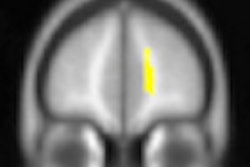

Researchers from Columbia University investigated neuroanatomical characteristics on preoperative MRI to see which OCD patients would respond to a procedure known as dorsal anterior cingulotomy, which involves lesioning, or damaging, a region of the brain associated with the neural network that causes OCD.

The researchers found that features of the anterior cingulate cortex structure and connectivity seemed to predict whether a patient would respond to the surgical treatment.